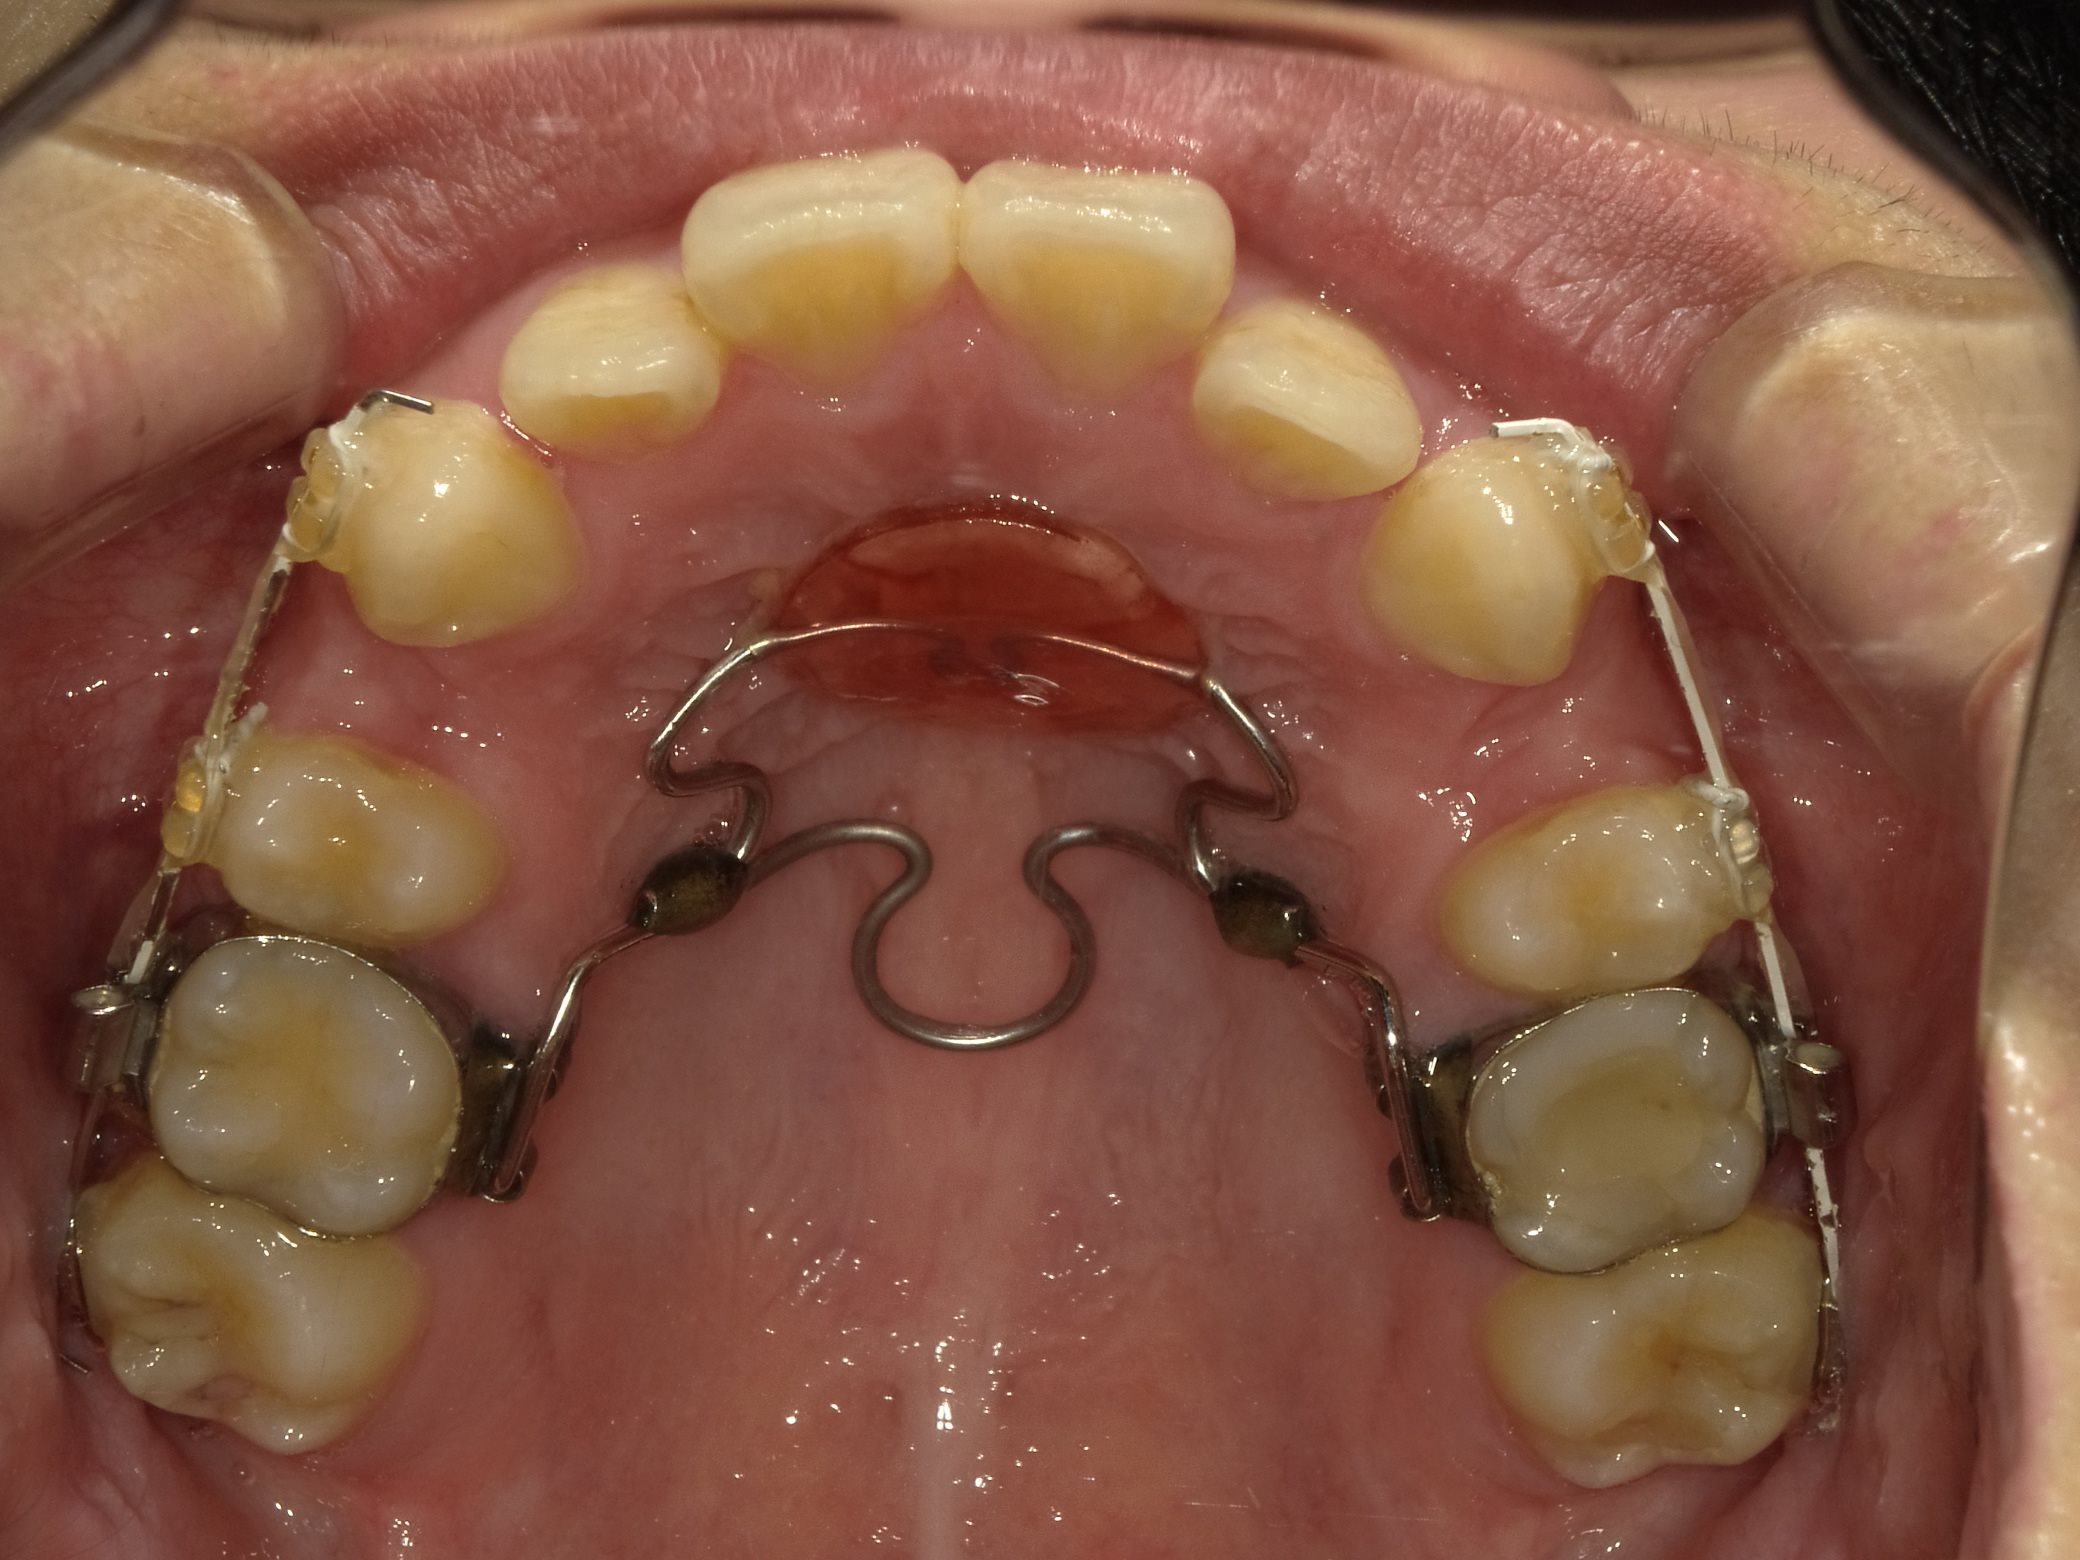

初診時の写真です。

上下とも顎の骨の大きさに対して歯が大きく、入りきっていないため、がたつきができています。

上下の歯を抜歯し、まずは奥歯にのみ装置がつきます。

また、前歯を下げる際にその力に負けて後ろの歯が前にきてしまうのを防ぐため、上顎の部分に固定のための装置を取り付けます。

歯の動きを見ながら、前歯にも装置を取り付けていきます。

下のワイヤーが曲がっているのが分かると思います。

ワイヤーを交換したり、力の掛け方を調整しながらこの歪みを治していきます。